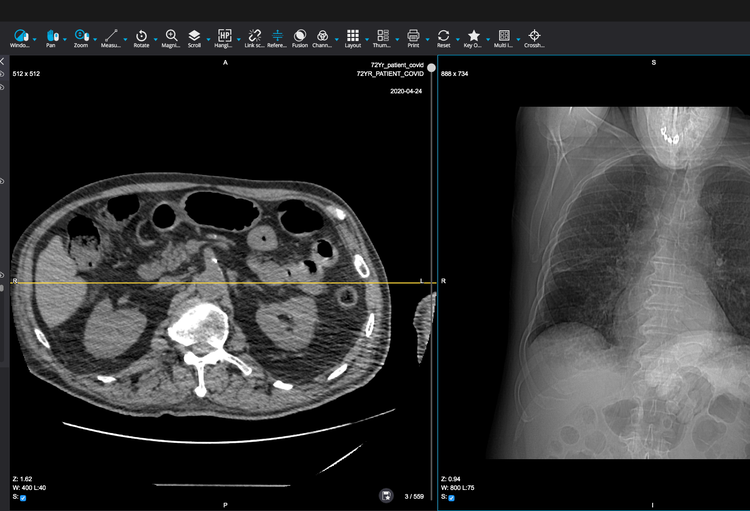

Accessible n'importe où via une connexion internet, et sans restriction vis-à-vis de la plateforme ou du langage informatique utilisé, Orthanc et l’interface d’utilisation développée spécialement par Osimis pour les médecins permettent une consultation d'images sécurisée à distance et des échanges d’informations plus faciles et rapides entre experts d’hôpitaux distincts.

> Vous pouvez également jeter un coup d’oeil à la démo en cliquant ici